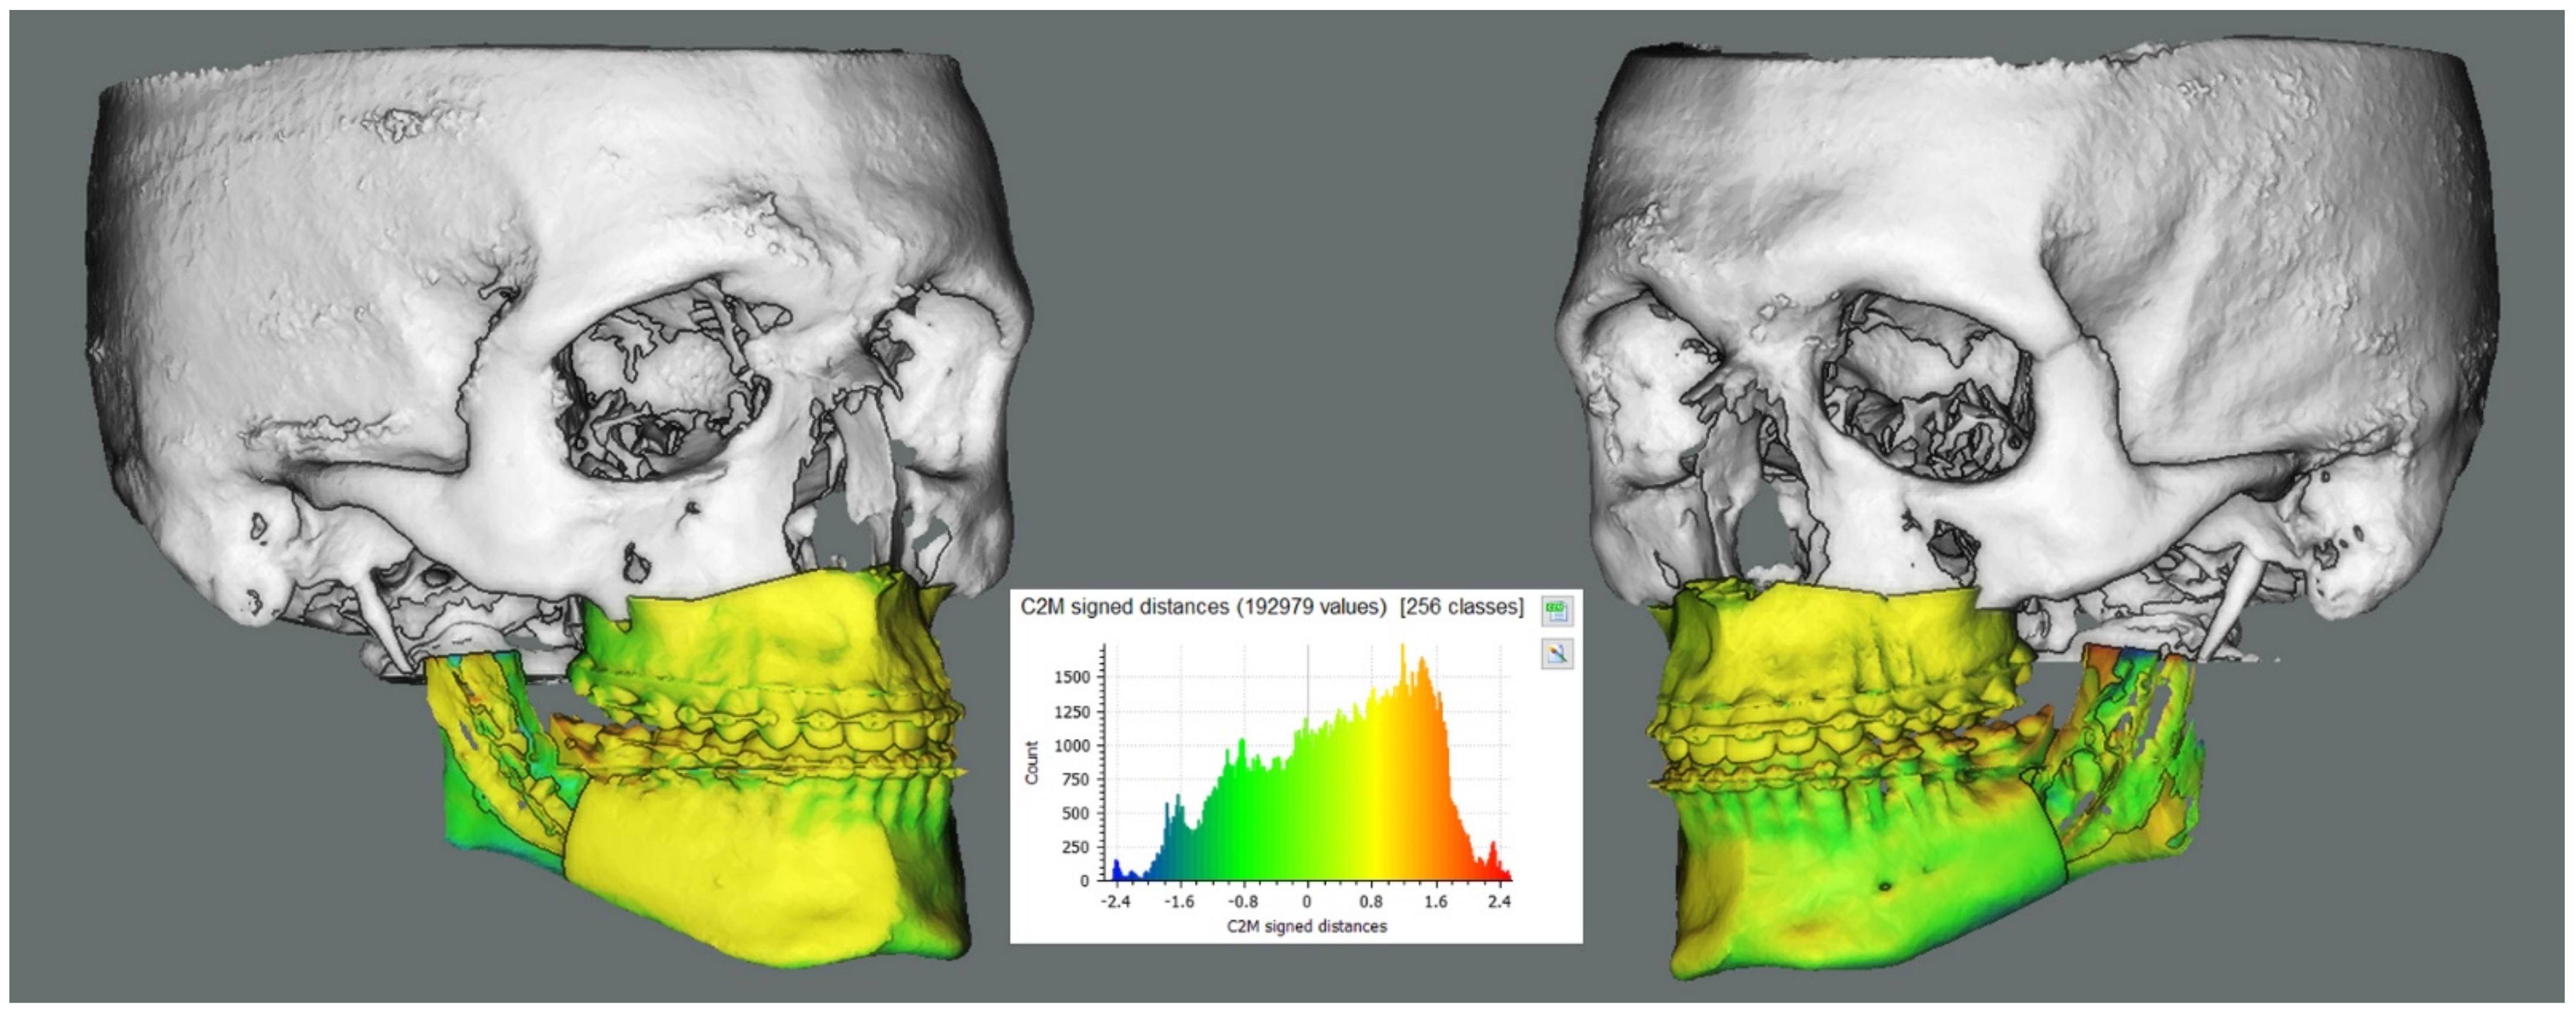

2.2. Outcome Analysis

3.1. Rigid Body Transformation Outcomes